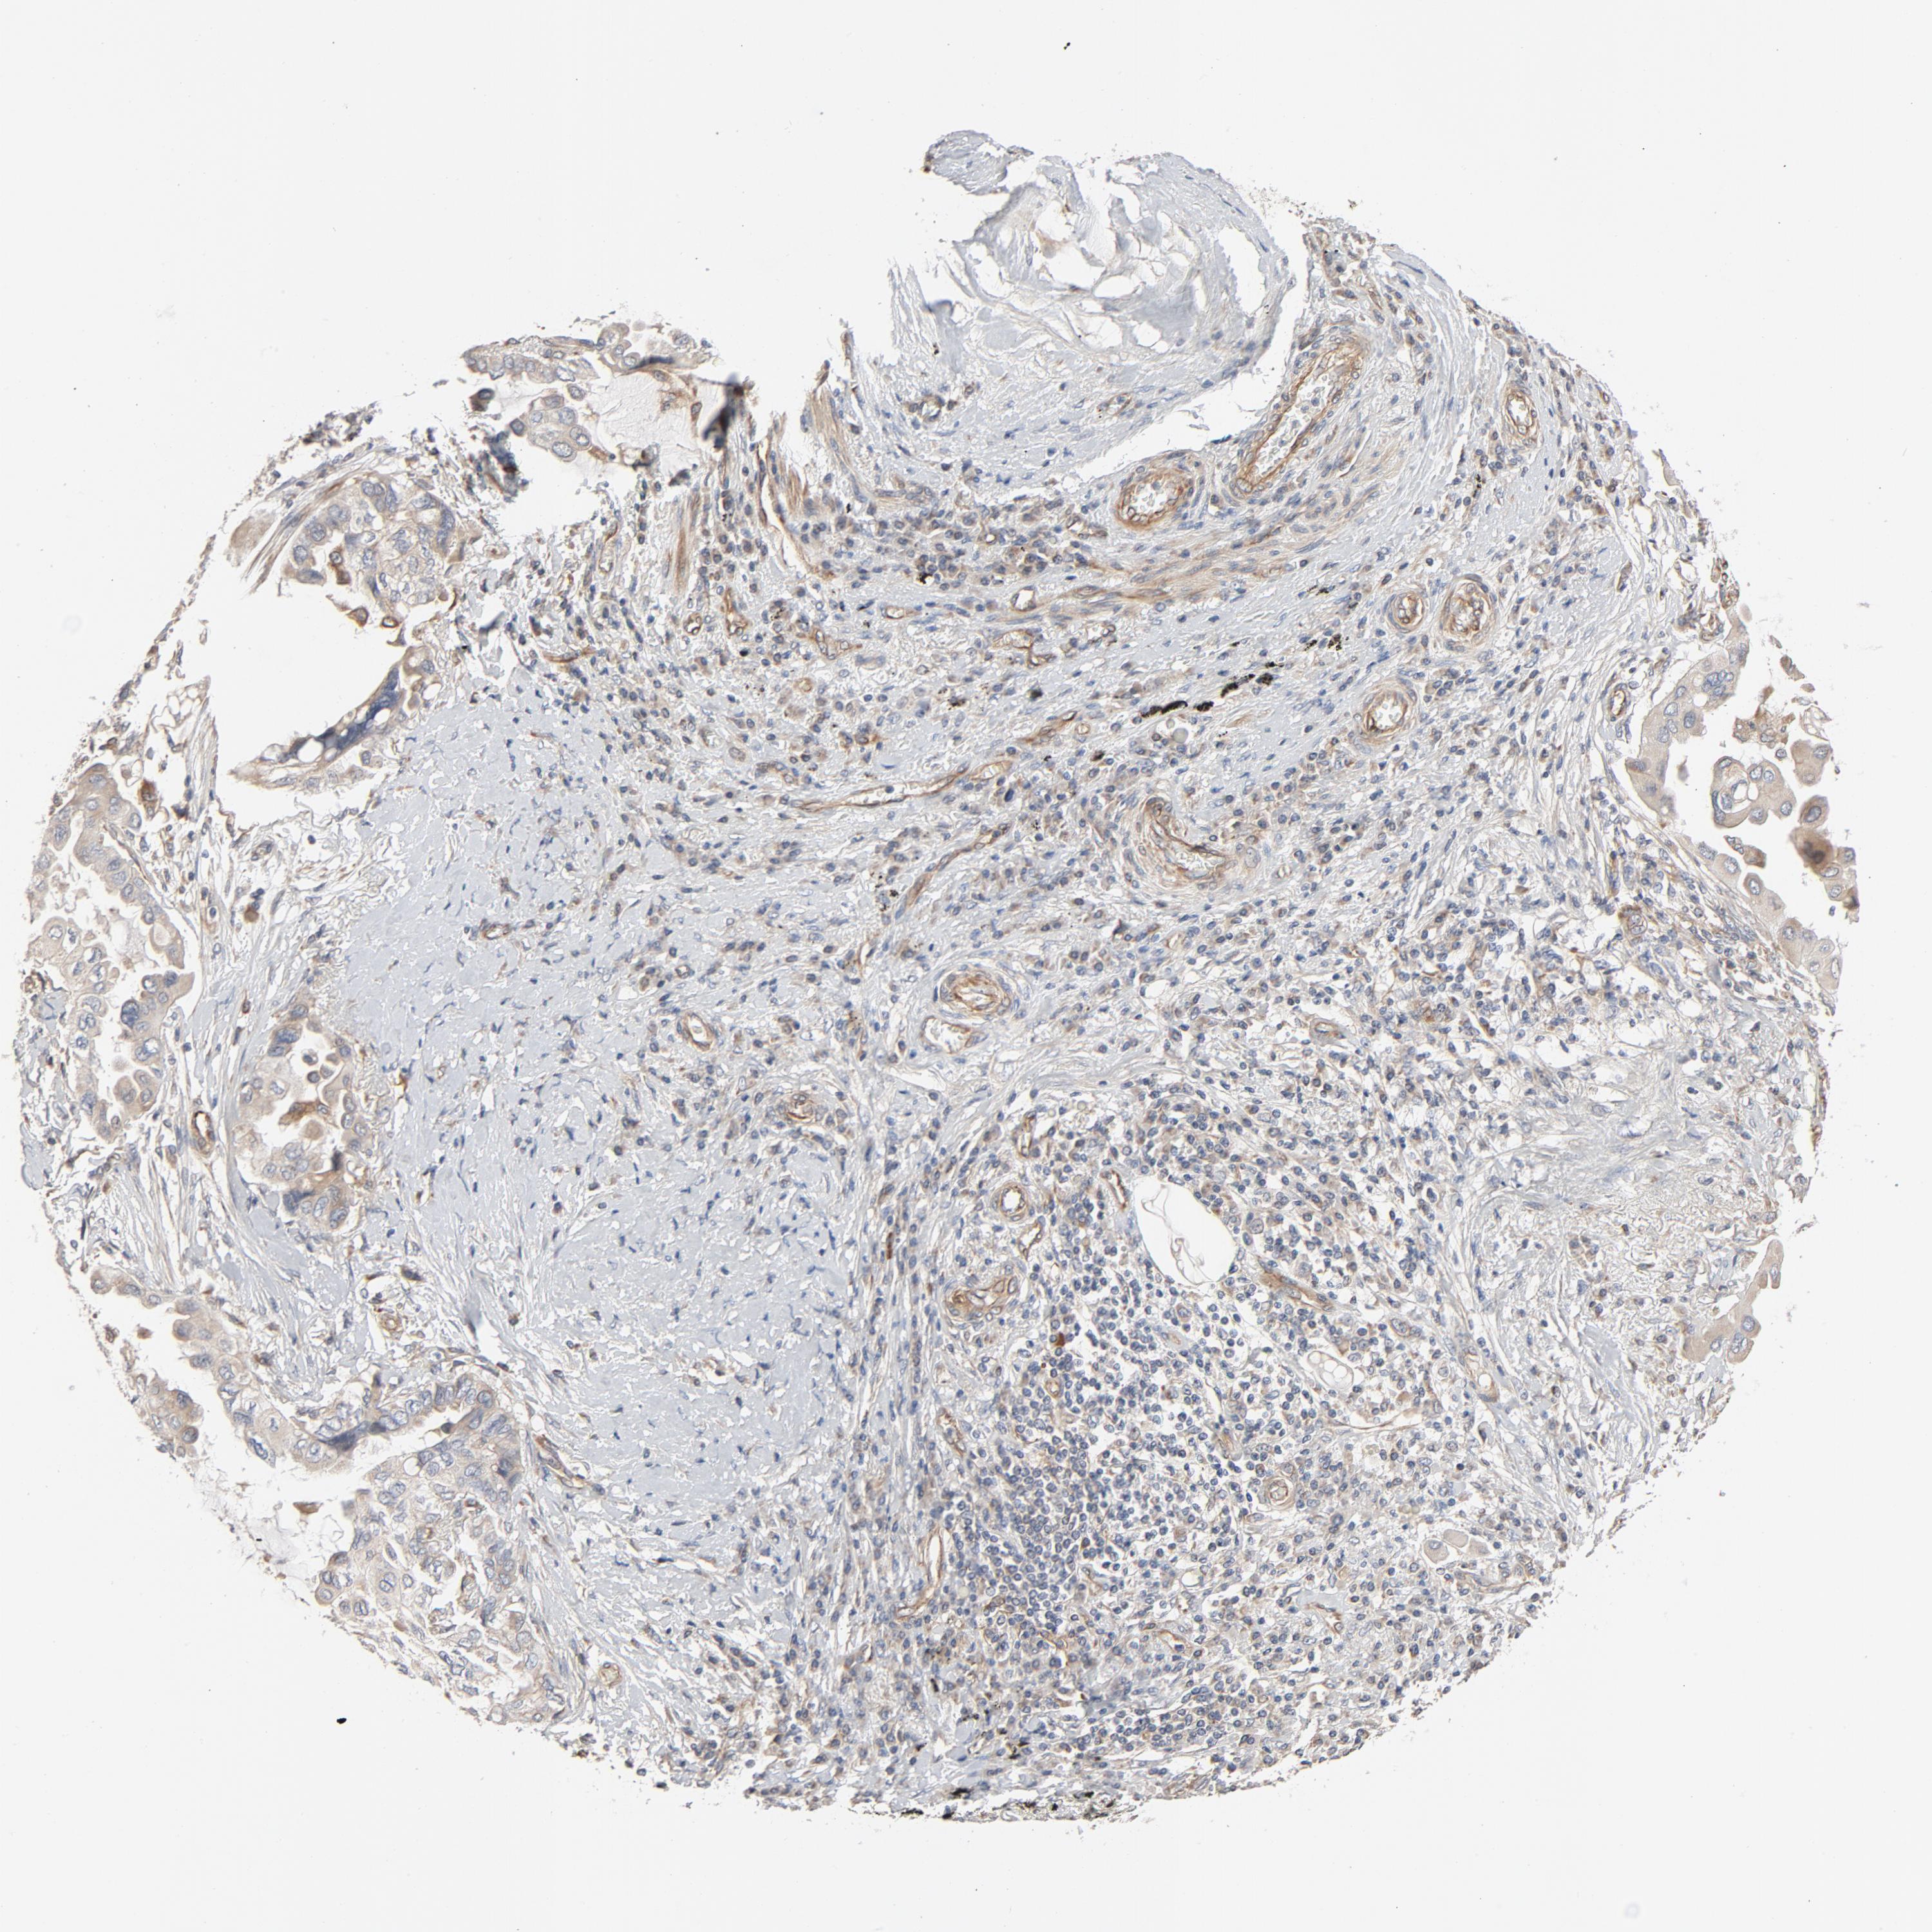

LUNG SQUAMOUS CELL CARCINOMA (TCGA) - Interactive survival scatter ploti

The Survival Scatter plot shows the clinical status (i.e. dead or alive) for all individuals in the patient cohort, based on the same data that underlies the corresponding Kaplan-Meier plots. Patients that are alive at last time for follow-up are shown in blue and patients who have died during the study are shown in red.

The x-axis shows the expression levels (FPKM) of the investigated gene in the tumor tissue at the time of diagnosis. The y-axis shows the follow-up time after diagnosis (years). Both axes are complimented with kernel density curves demonstrating the data density over the axes. The top density plot shows the expression levels (FPKM) distribution among dead (red) and alive patients (blue). The right density plot shows the data density of the survived years of dead patients with high and low expression levels respectively, stratified using the cutoff indicated by the vertical dashed line through the Survival Scatter plot. This cutoff is automatically defined based on the FPKM cutoff that minimizes the p-score. The cutoff can be changed by dragging the vertical line or by entering a cutoff value in the square labeled "Current cut-off".

Under the Survival Scatter plot the p-score landscape (black curve; left axis) is shown together with dead median separation (red curve; right axis). Dead median separation is the difference in median mRNA expression between patients who have died with high and low expression, respectively. It is calculated as follows: median FPKM expression of dead patients with high expression - median FPKM expression of dead patients with low expression. This is intended to aid the user in visually exploring custom cutoffs and the associated p-scores and dead median separation.

Individual patient data is displayed and can be filtered by clicking on one or more of the category buttons on the top of the page. Categories describing expression level and patient information include: high, low, alive, dead, female, male and tumor stages. The scale of the x-axis can be toggled between linear and log-scale by clicking on the "x log" button. Mouse-over function shows TCGA ID, patient information and mRNA expression (FPKM) for each patient.

& Survival analysisi

Kaplan-Meier plots summarize results from analysis of correlation between mRNA expression level and patient survival. Patients were divided based on level of expression into one of the two groups "low" (under cut off) or "high" (over cut off). X-axis shows time for survival (years) and y-axis shows the probability of survival, where 1.0 corresponds to 100 percent.

TRIOBP is not prognostic in Lung Squamous Cell Carcinoma (TCGA)

Current cut offi

Current cut-off shows the cut-off (FPKM) currently selected. It may be changed manually. When the current cut-off is changed, the vertical dashed line indicating cut-off, the interactive survival scatter plot and the Kaplan-Meier curve will be automatically adjusted to show results accordingly.

:

Best expression cut offi

Based on the FPKM value of each gene, patients were classified into two groups and association between prognosis (survival) and gene expression (FPKM) was examined. The best expression cut-off refers the FPKM value that yields maximal difference with regard to survival between the two groups at the lowest log-rank P-value. Best expression cut-off was selected based on survival analysis .

When clicking on this number, the vertical dashed line indicating cut-off, the interactive survival plot, and the Kaplan-Meier curve will be adjusted to show results based on the best expression cut-off.

: 35.81

Median expressioni

Median expression refers to the median FPKM value calculated based on the gene expression (FPKM) data from all patients in this dataset. When clicking on this number, the vertical dashed line indicating cut-off, the interactive survival plot, and the Kaplan-Meier curve will be adjusted to show results based on the median expression.

: N/A

Median follow up timei

Median follow up time refers to the median time (years) after diagnosis with this type of cancer, based on clinical data from all patients in this dataset.

P scorei

Log-rank P value for Kaplan-Meier plot showing results from analysis of correlation between mRNA expression level and patient survival.

N/A

5-year survival highi

5-year survival for patients with higher expression than the expression cutoff.

For melanoma and glioma, 3-year survival is shown.

5-year survival lowi

5-year survival for patients with lower expression than the expression cutoff.

TCGA RNA samplesi

RNA-seq data is reported as average FPKM (number Fragments Per Kilobase of exon per Million reads), generated by the The Cancer Genome Atlas (TCGA) .

Normal distribution across the dataset is visualized with box plots, shown as median and 25th and 75th percentiles. Points are displayed as outliers if they are above or below 1.5 times the interquartile range. FPKM values of the individual samples are presented next to the box plot.

Average pTPM 39.7

Number of samples 489